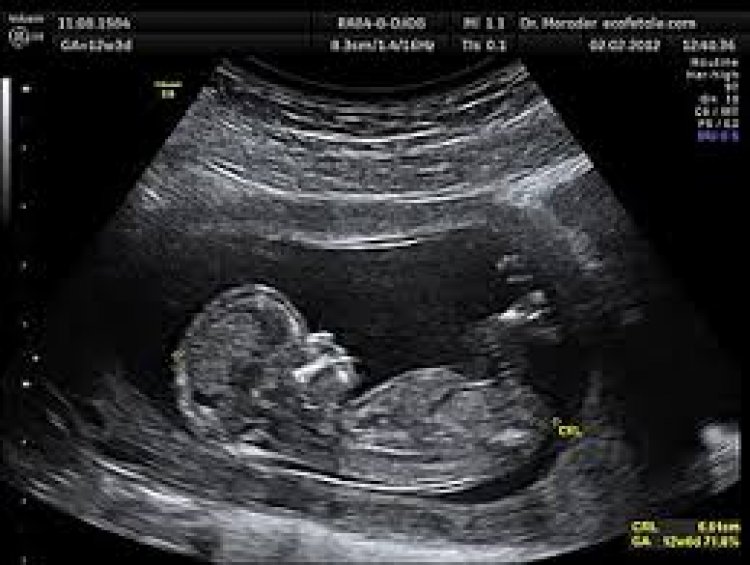

उच्च जोखिम वाली 1667 गर्भवती महिलाओं का किया गया नि:शुल्क सोनोग्राफी

राजनांदगांव। जिले में उच्च जोखिम वाली गर्भवती महिलाओं का नि:शुल्क जांच एवं उपचार किया जा रहा है। अब तक 1667 उच्च जोखिम वाली गर्भवती महिलाओं की सोनोग्राफी की जा चुकी है। प्रधानमंत्री सुरक्षित मातृत्व अभियान अंतर्गत जिले में गर्भवती महिलाओं को प्रसवपूर्व देखभाल उपलब्ध कराने प्रत्येक माह की 9 एवं 24 तारीख को विशेष स्वास्थ्य शिविरों का आयोजन किया जा रहा है।

कलेक्टर जितेन्द्र यादव के निर्देशानुसार प्रधानमंत्री सुरक्षित मातृत्व अभियान अंतर्गत उच्च जोखिम वाली गर्भवती महिलाओं को प्रत्येक सप्ताह दूरभाष के माध्यम से स्वास्थ्य संबंधी आवश्यक जानकारी एवं सलाह दी जा रही है। मुख्य चिकित्सा एवं स्वास्थ्य अधिकारी डॉ. नेतराम नवरतन ने बताया कि प्रधानमंत्री सुरक्षित मातृत्व अभियान अंतर्गत जिले में 1775 उच्च जोखिम वाली गर्भवती महिलाएं है। जिसमें 1667 उच्च जोखिम वाली गर्भवती महिलाओं का सोनोग्राफी किया गया है एवं शेष 108 गर्भवती महिलाओं का शनिवार तक सोनोग्राफी कर लिया जाएगा। उन्होंने बताया कि इंडियन मेडिकल एसोसिएशन की मदद से आज कुल 16 गर्भवती महिलाओं का नि:शुल्क सोनोग्राफी किया गया है। जिसमें सुन्दरा अस्पताल में घुमका के 11 एवं भारत डायग्नोस्टिक में 5 गर्भवती महिलाओं का नि:शुल्क सोनोग्राफी किया गया है।